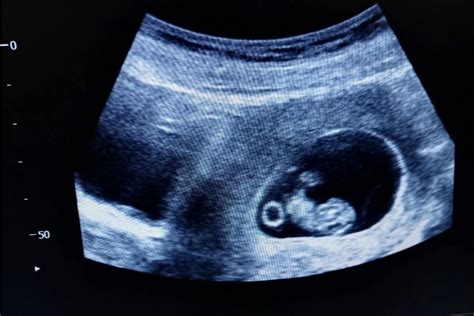

Častou otázkou nastávajúcich mamičiek je, kedy prvýkrát uvidia plod na ultrazvuku a kedy im lekár potvrdí, že sa vajíčko úspešne uhniezdilo v maternici. Vo všeobecnosti sa za zlomový považuje 6. týždeň tehotenstva. Ultrazvuková vizualizácia začínajúceho vnútromaternicového tehotenstva je možná už v období 5. týždňa. V ideálnom prípade možno vidieť nielen gestačný vak, ale aj jeho obsah. Ak si žena urobila tehotenský test a vyšiel pozitívne, lekári zvyčajne odporúčajú prvú návštevu medzi 6. a 8. týždňom. V prípade znepokojujúcich príznakov - ako je silná bolesť, krvácanie alebo predchádzajúce problémy s tehotenstvom - môže byť ultrazvuk vykonaný aj v 5. týždni.

Počas prvého ultrazvukového vyšetrenia je možné počuť tlkot srdca plodu a určiť jeho srdcovú frekvenciu.

Ultrazvuk v 1. Trimestri (6. - 12. týždeň)

Základným ultrazvukovým vyšetrením v tehotenstve je ultrazvuk v 1. trimestri, ktorý prebieha približne v 6. až 12. týždni tehotenstva. Lekár sa zameriava na základné parametre tehotenstva:

- Stanovenie dĺžky tehotenstva: Je veľmi dôležité najmä u žien s nepravidelným menštruačným cyklom, aby lekár správne stanovil očakávaný dátum pôrodu. Ideálne je absolvovať toto meranie v 8. až 9. týždni. Fázy od 9. - 11. týždňa gravidity stanovujeme tzv. CRL (temenokostrná vzdialenosť) rozmer embrya. Práve toto obdobie je najoptimálnejšie pre meranie CRL a tým stanovenie čo najpresnejšieho odhadu termínu pôrodu (odchýlka +-4,7 dňa).

- Potvrdenie životaschopnosti plodu: Srdiečko vidno pulzovať od 6. až 7. týždňa.

- Vylúčenie mimomaternicového tehotenstva: Cieľom je potvrdiť prítomnosť embrya v maternici a vylúčiť možnosť mimomaternicovej gravidity už v 6. týždni tehotenstva.

Vyšetrenie v prvom trimestri zobrazuje: termín počatia; štruktúru a tonus maternice; miesto uchytenia placenty; počet embryí; veľkosť plodu. Počas vyšetrenia je možné určiť riziko nedonosenia plodu a riziká abnormalít embrya.